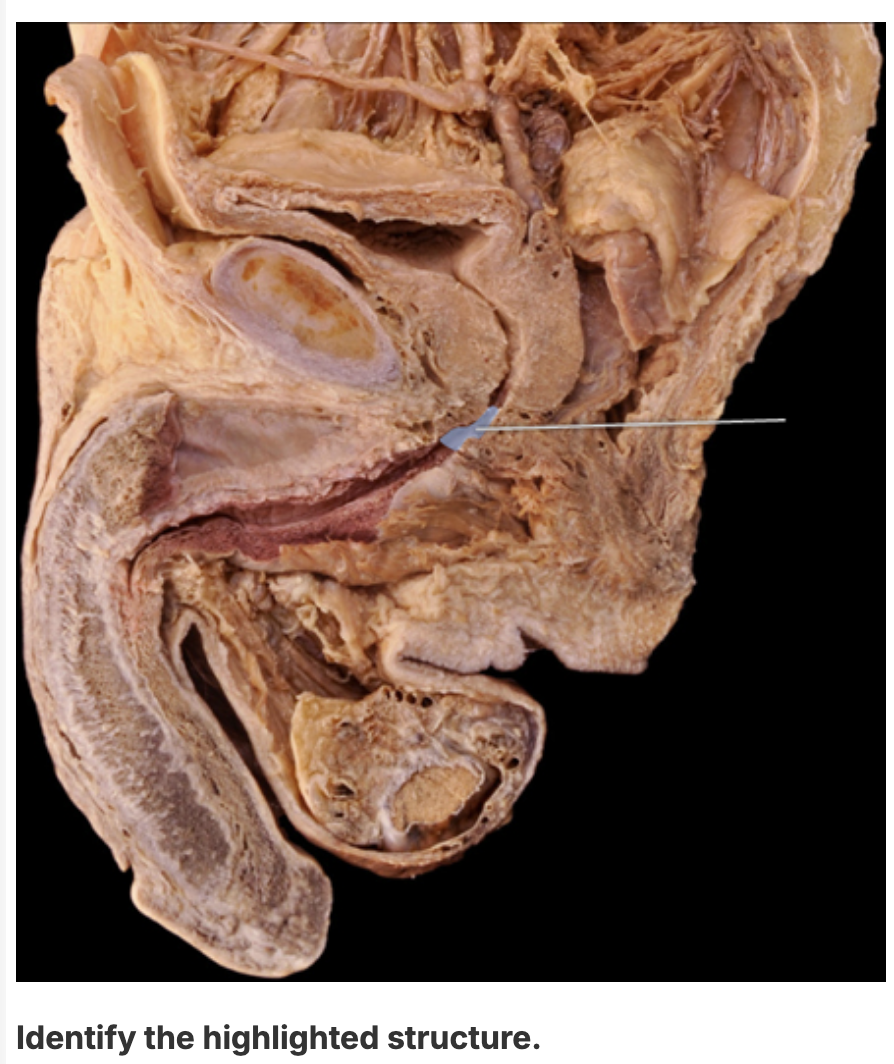

membranous urethra